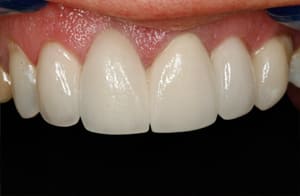

Thank you to our patients that have allowed us to show examples of our work

Have a look at just some of the many patient examples we have captured from BEFORE and AFTER their treatments and cosmetic surgeries.

From Whitening to Veneers, Fillings to Cosmetic Teeth Makeovers, here are some examples of the work that Dr. Dadabhai has provided to his patients to give them a more confident smile and a positive, pain free feeling.

Much of the work we carry out is to relieve pain and of course maintain the health of your teeth and gums, but many of our patients now ask for Cosmetic work to give them a more confident smile.

Cosmetic support has improved hugely over the last few years. Book a Consultation with Dr Dadabhai and he will prescribe a course of treatment to complete your perfect SMILE transformation.